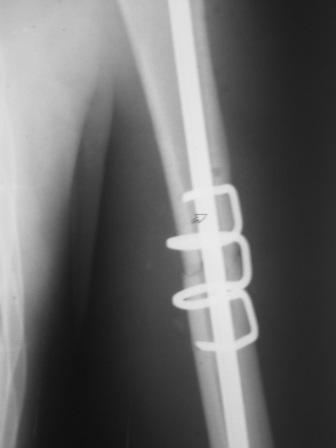

[Ortho] Перелом н\3 плечевой кости. Тактика лечения?

Да, как раз блокированная пластина и стоит, не синтезовская метадиафизарная, Рыбинская, но на порядок дешевле, а профилактика всех осложнений - в данном конкретном случае, начало ранней на вторые сутки - после удаления дренажа разработки движений в смежных суставах. Если же идти с ревизией т.е. всё равно, открыто как вариант небольших разрезов при поперечном переломе можно и комбинированный мос (см.на вкладыше), хотя думаю для такого способа перелом всётаки низковат.